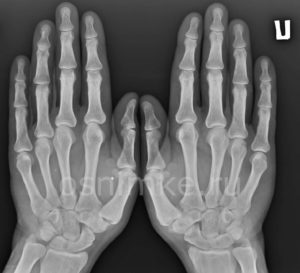

Рентген руки — метод исследования костных структур на предмет наличия переломов, трещин, остеопороза и других патологий. Рентгенография — современная и безопасная медицинская процедура.

Снимок руки помогает выявить заболевания костной, хрящевой, мышечной, соединительной ткани на ранних этапах, когда симптоматика болезни ещё не развилась и человек даже не подозревает о наличии у себя патологии.

При наличии подозрения на повреждение связочного аппарата, ушибы, переломы или вывихи, доктор назначит рентген кисти. На полученном снимке отчётливо видны патологические изменения. Перелом кисти рентгенологически проявляется линией просветления, нарушением целостности надкостницы, её подрытыми краями и др.

Показано регулярно делать снимок кисти с целью контроля над процессами репарации тканей. Процедура широко используется в криминалистике. Она определяет возраст пациента (костный возраст), устанавливает пол, род занятий человека.

Рентген кисти руки позволяет выявить такие заболевания и травмы, как переломы, вывихи, артрит, остеопороз, опухоли и другие патологии костей и суставов.

Целью проведения рентгенографии кисти руки является получение детального изображения костей, суставов и мягких тканей для выявления патологий, диагностики травм и контроля за эффективностью лечения.